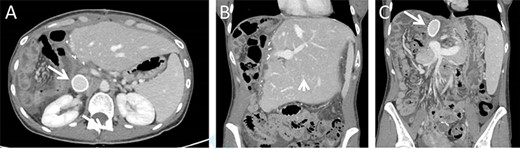

Surgical exploration via right subcostal incision with midline extension was performed. A giant tumour encompassing the entire right lobe including the middle hepatic vein as well as the caudate lobe and retrohepatic IVC was demonstrated. Femoral-Jugular venous–venous bypass was used during an en-bloc resection of the right hemi-liver, most of segment four, the caudate lobe, and approximately a 10 cm section of the retrohepatic IVC (Fig. 2). Reconstruction of the IVC was performed using a 20 mm Gore-tex graft (Fig. 2). A 20-minute bypass time was required. The surgery went uneventful with minimal blood loss. No blood products were administered during the operations.

Intraoperative images. Intraoperative image depicting the remnant left lateral segment drained by the left hepatic vein into the IVC stump, marked by an arrow (A), and following IVC reconstruction with Gore-tex graft (B).